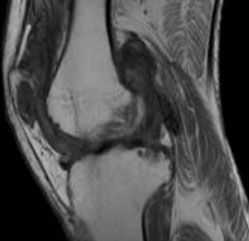

Rheumatoid arthritis

Morning stiffness that lasts >30 min and improves c use

*** in RA morning stiffness lasts a Really long time***

- symmetric synovial joint involvement and systemic symptoms

-- synovial fluid studies show: dec viscosity, dec C3, inc WBCs

Type III Hypersensitivity

~80% have positive rheumatoid factor (anti-IgG ab)

-- synovial cells express an antigen that cross-reacts c B-cell receptors stimulating B-cells to become plasma cells and produce RF (an ab that binds the Fc of IgG)

- anti-CCP ab less sensitive but more specific

-- strongly assoc c HLA-DR4

Features:

Pannus is granulomatous tissue rich in inflam cells and fibroblasts in joint space that proliferates and releases cytokines (TNF-a and IL-1) causing a cell-mediated destruction of articular cartilage and eventual ankylosis (a type IV HS)

- Carpal tunnel from flexor-tenosynovitis or median n compression from swelling

-- Rheumatoid synovitis on micro shows villous formation, hyperplasia/hypertrophy of the lining cells, fibrinoid necrosis and chronic inflam in the synovial membrane (tx'd surgically c physiotx)